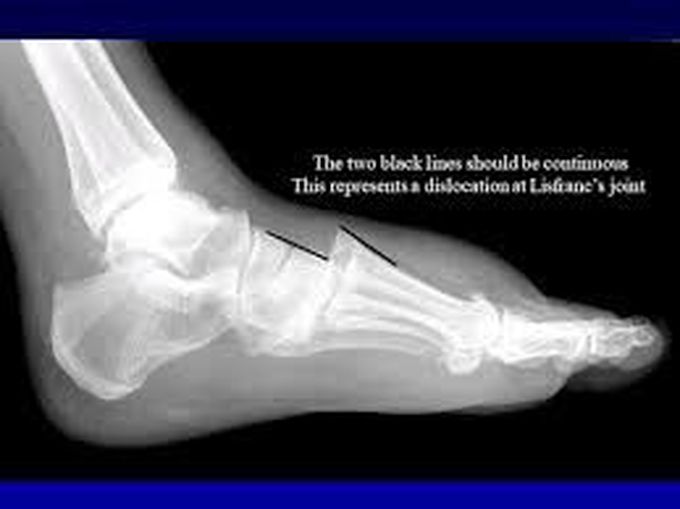

Comprehensive Recovery Process After A Lisfranc Injury Fracture.

Lisfranc fractures often occur when a person steps in a hole and the toes become caught,. It’s important to rest your injured area as much as possible in the first 24 to 72 hours.